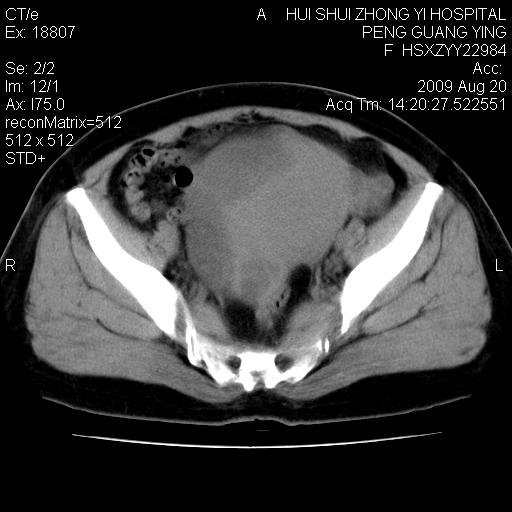

标题: CT21707:女,42岁,因发现下腹部包块2月。 [打印本页]

标题: CT21707:女,42岁,因发现下腹部包块2月。

目前的影像表现显示肿块位于腹腔及盆腔,但具体定位,分清来源较困难,是否来源于卵巢、子宫无法定论,子宫直肠及子宫膀胱周围脂肪间隙尚较清晰,如果患者有过腹腔好或者盆腔手术史,也可以形成不典型的血中,最好手术后定为定性,我期待结果。

软组织密度,与子宫一致。双侧卵巢形态、密度好,不支持来源于卵巢。

来源卵巢--畸胎类肿瘤

病史不全面,病灶来源可能是子宫或卵巢,若临床有剖腹产、痛经史,则更支持前者,亦更支持子宫腺肌症